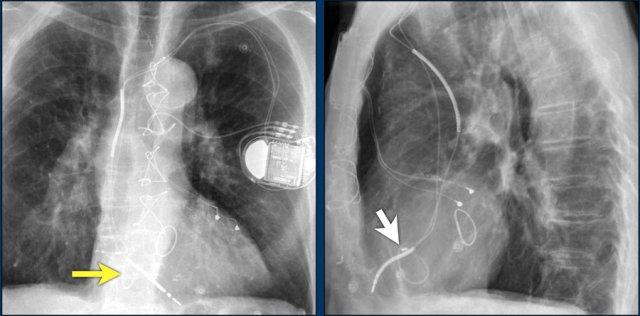

Hội chứng Twiddler

Hội chứng Twiddler là tình trạng máy tạo nhịp tim hoạt động không bình thường do bệnh nhân tự tác động vào thiết bị, dẫn đến lệch vị trí các điện cực.

Hậu quả là máy tạo nhịp hoạt động sai chức năng hoặc đôi khi kích thích các cấu trúc khác như thần kinh hoành hoặc đám rối thần kinh cánh tay.

Hình ảnh bên trái cho thấy bệnh nhân có ICD được đặt đúng vị trí.

Vài tháng sau, thiết bị hoạt động không bình thường do hộp ICD và điện cực bị xoay (mũi tên vàng) và co rút lại (mũi tên trắng).

Đây là một bệnh nhân khác mắc hội chứng Twiddler.

Lưu ý hình ảnh điện cực bị cuộn xoắn gần máy tạo nhịp và tại đầu điện cực trong thất phải (mũi tên).